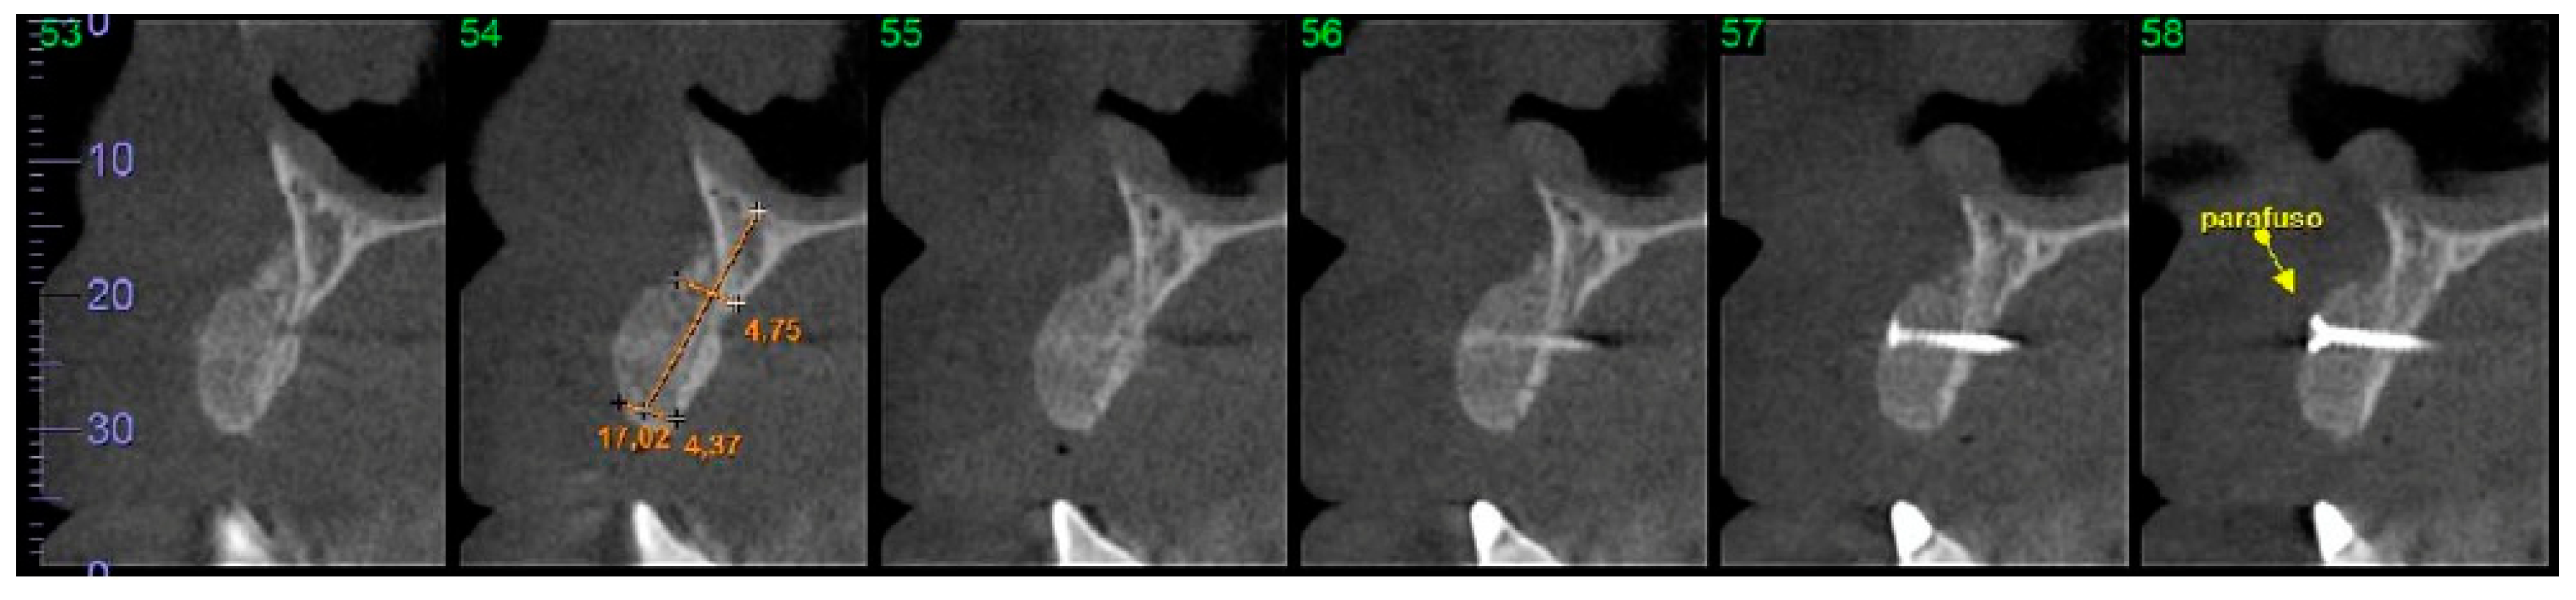

2.7. Computed Tomographic (CT) Evaluation